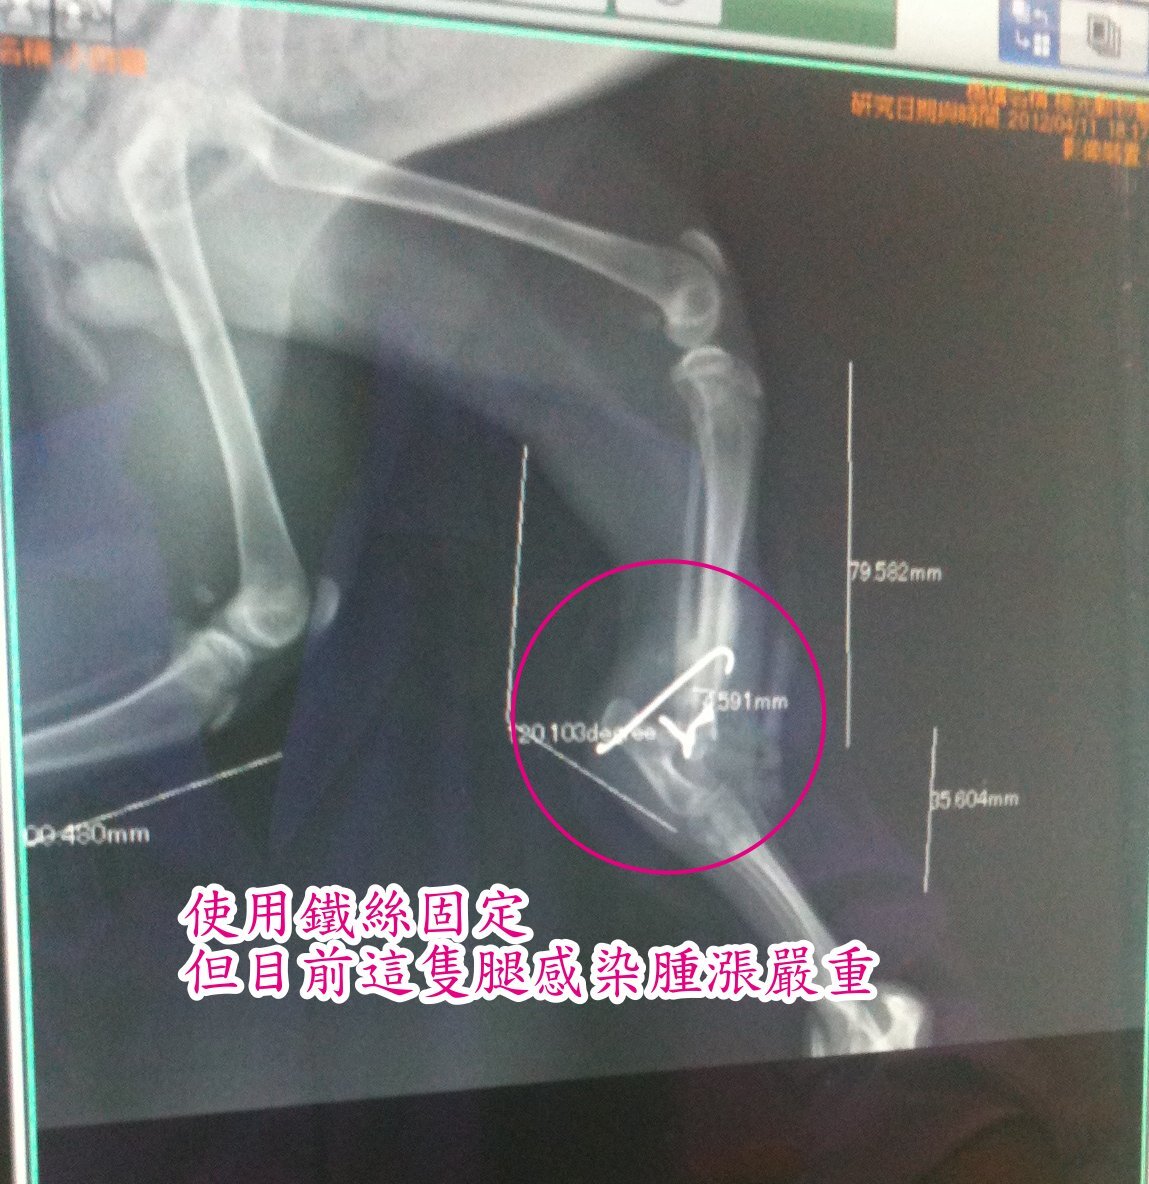

經由X光片可看到右前肢肩頰骨處、右後腿的關節蓋已於第一次手術中被切除,

並用鐵絲固定,

看得出手術不成功,

也造成後腿腫脹與嚴重感染。

原醫院做出截掉右前肢、右後腿決定,

這將造成貓咪日後完全無著力點行動與站立,

目前依第一次手術的施作結果,

若幸得保存兩腿,

但關結板已被切除、固定,

將造成日後關節無法彎曲。